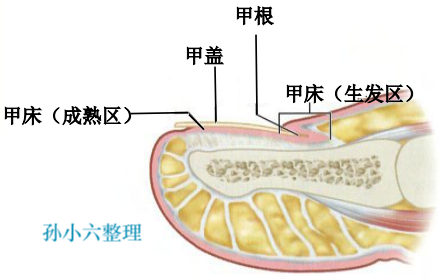

临床表现 (分 3 期)